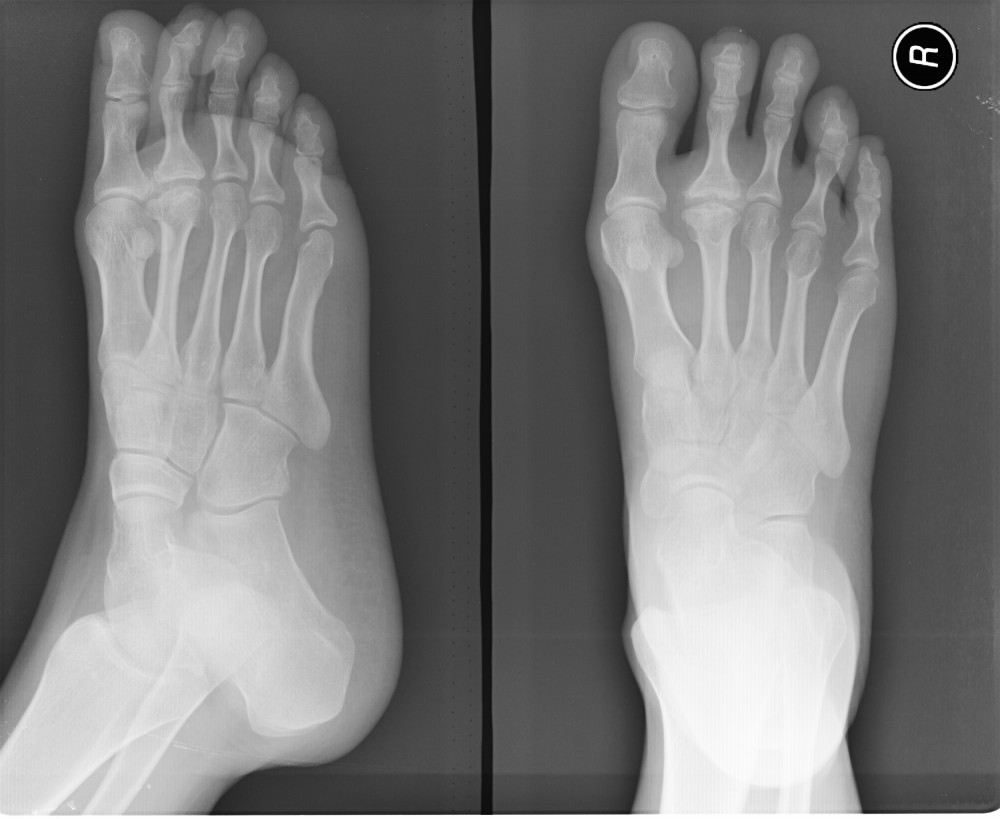

以下是引用拾荒者在2009-8-26 20:50:00的发言:[br]跖骨头骨骺缺血性坏死又称freiberg病或kö;hlerⅱ病。好发于第二跖骨,偶见于第三跖骨,第四跖骨罕见。发病以13~20岁最多,平均19岁。女性居多。发病与外伤、职业及劳动体位密切相关。[br]本例典型的跖骨头骨软骨炎并跖趾关节退行性变。